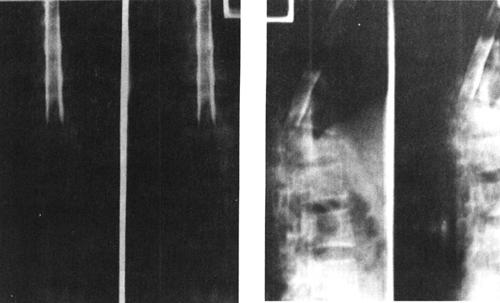

(二)脊髓造影

脊髓造影是一种有创伤性的检查,利用穿刺针向蛛网膜下腔内注入阳性造影剂使蛛网膜下腔和脊髓显影,从而了解脊髓受压情况和蛛网膜下腔的通畅情况。脊髓造影所用的造影剂为硬膜囊内注射专用碘造影剂,常用等渗非离子水溶性碘造影剂,其毒副作用小,很少产生过敏反应并且显影效果好。因而,脊髓造影仍然可作为了解脊髓病变的一种有效、安全的影像学检查方法,尤其对目前没有MRI设备的医院,脊髓造影仍然是了解椎管内病变的一种有效的检查方法(图7-3)。

图7-3 T12椎体压缩性骨折呈楔状改变,并向后突。脊髓造影显示,该水平蛛网膜下腔受压闭塞,呈双峰状